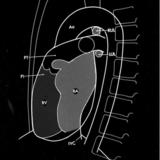

Right chambers PA

Date: 03/02/2006

Views: 2340